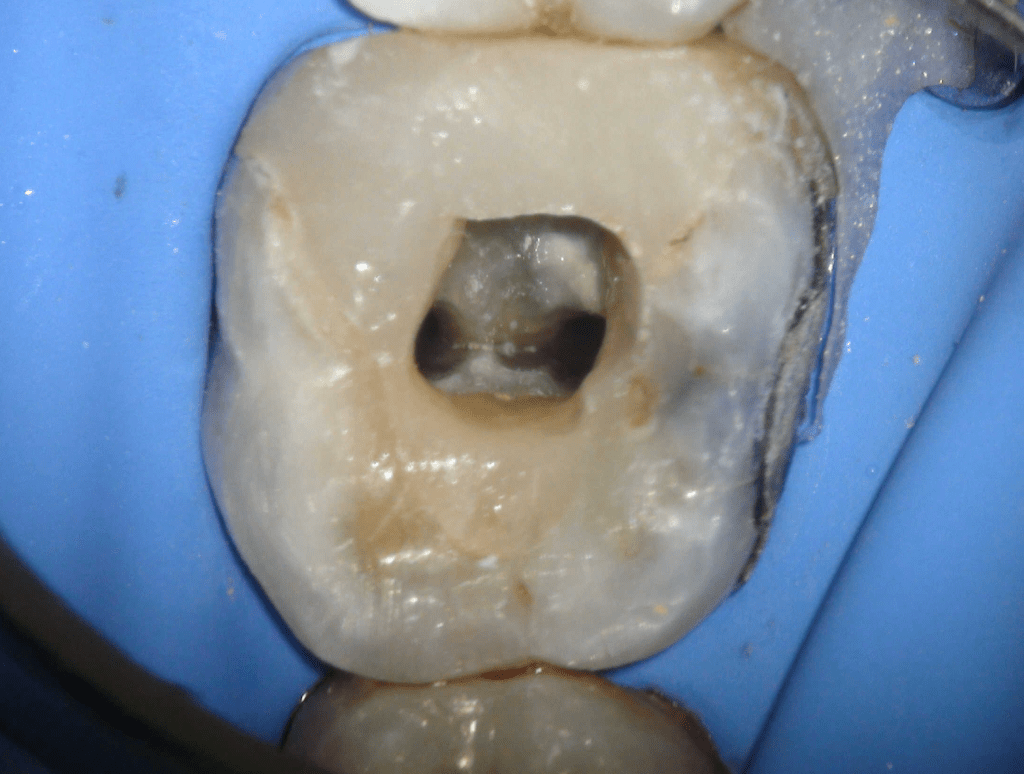

Fisura, remoción amalgama para explorar